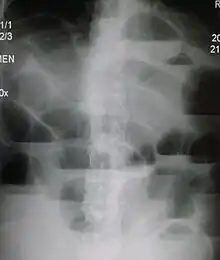

The main diagnostic tools are blood tests, X-rays of the abdomen, CT scanning, and ultrasound. If a mass is identified, biopsy may determine the nature of the mass.

Radiological signs of bowel obstruction include bowel distension (small bowel loops dilated >3 cm) and the presence of multiple (more than 2) air-fluid levels on supine and erect abdominal radiographs.[16] Ultrasounds may be as useful as CT scanning to make the diagnosis.[17]

Contrast enema or small bowel series or CT scan can be used to define the level of obstruction, whether the obstruction is partial or complete, and to help define the cause of the obstruction. The appearance of water-soluble contrast in the cecum on an abdominal radiograph within 24 hours of it being given by mouth predicts resolution of an adhesive small bowel obstruction with sensitivity of 97% and specificity of 96%.[18]